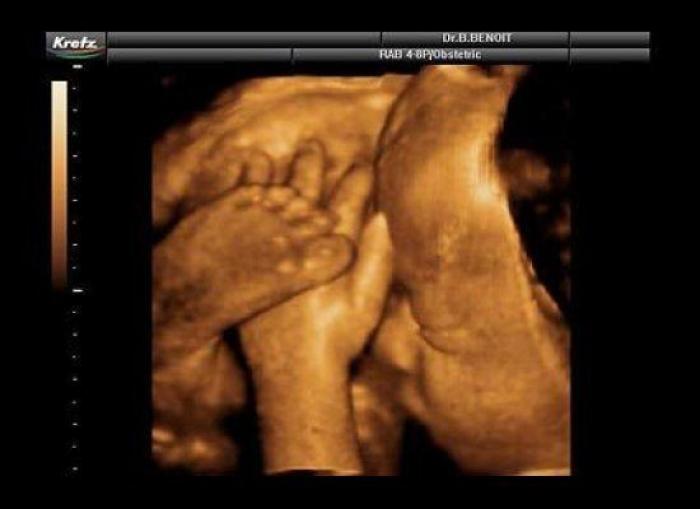

En esta galería puedes ver en fotos como es el desarrollo de un feto de semana en semana:

Desarrollo del feto, en fotos